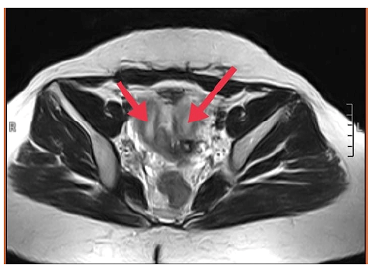

Solid Pseudopapillary Tumor of the Pancreas: A Case Report

Lamara Abdelhak, Medjahdi Sid Ahmed, Gadda Mounir, Boukhane Mohamed, Nahida Harchouche, Bloulou Mamed Lamine, Saadna Adlene and Selmani Khaled. 6(7): 12-18.